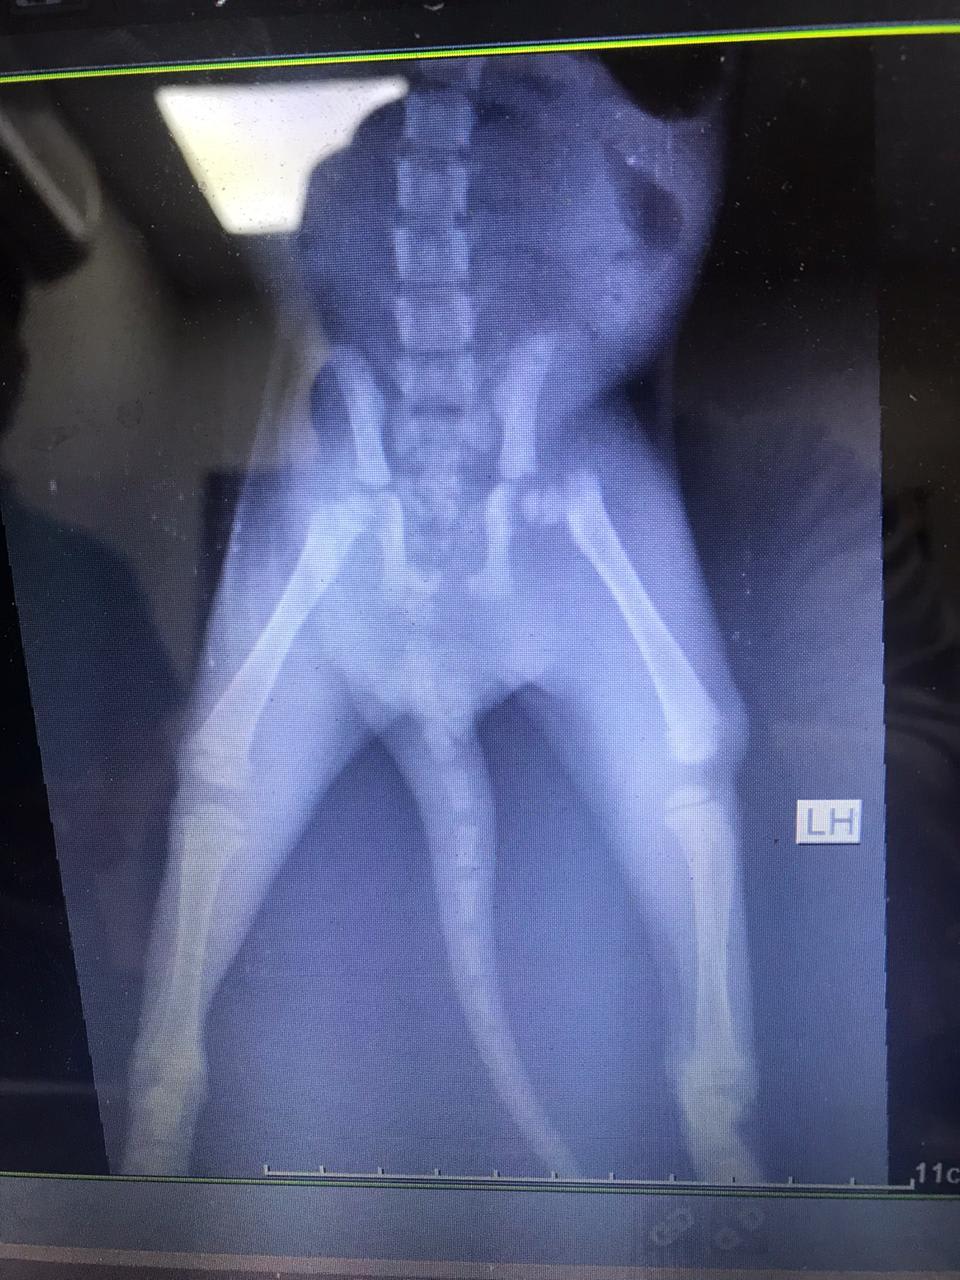

Stray cat estimated 3 months old found with presumed broken hip and leg. Took him to 3 vets but we live in a country where vets aren’t the best and they said there’s nothing we can do he’s too small to go into surgery. What do you recommend we do? Should we give him a makeshift cast? If so, how?

It's a little difficult to see in your copy of the x-ray, but it looks like the left femur might be fractured. If the broken bone is above the knee then a cast won't help because it's not possible to stabilize the fracture. If they have recommended pain medication and rest I think that probably is the best option with a broken hip - kittens can heal quickly and it's possible that he will have decent function in the leg. If not, then a surgery called a femoral head osteotomy might be an option once he's big enough for surgery.